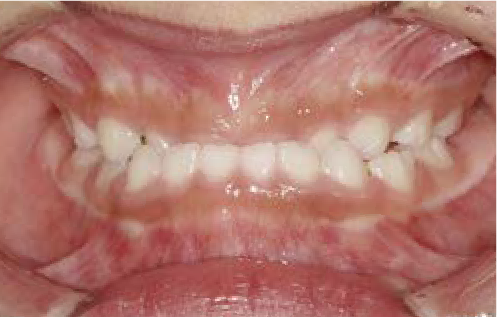

現役歯科医師の愛娘さんの治療

Nさん (矯正開始時:8歳)

Before

After

上あごの成長が少なく、特に前歯のガタガタが目立っていました。口呼吸のクセや飲み込み方に良くないクセが確認されました。

治療を終えて

マイオブレイスとBB1装置で上あごの成長を助け、鼻呼吸や正しい飲み込み方を身につけることで、きれいな歯並びとしっかり噛めるお口に変わっていきました。

姿勢やお口の機能を正しく整えたので、後戻りしない綺麗な歯並びを維持できています。もちろん非抜歯です。

主訴・治療内容 当院と交流のある歯科医師の先生が、ご自身のお子さまの治療を任せてくださいました。

「難しい歯並びでも永久歯を抜かず、全身の健康と顔立ちも考えて治療してくれる」と信頼していただいて治療開始。

治療期間 3年

費用 462,000円(税込)